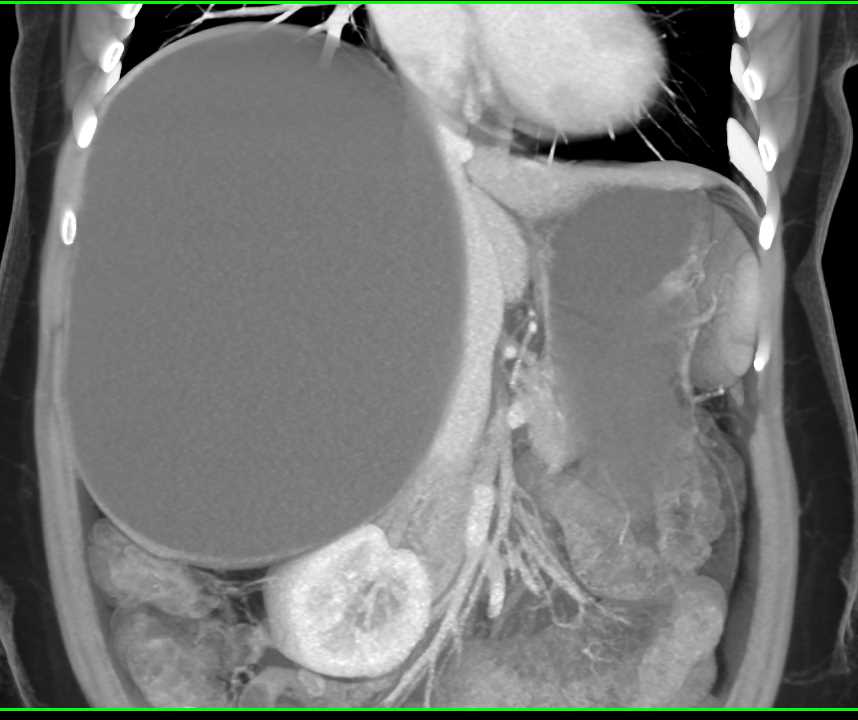

Large Simple Hepatic Cyst – Liver Case Studies – CTisus CT Scanning

Healthy Liver, Ct Scan Photograph by Zephyr

Healthy Liver, Ct Scan Photograph by Zephyr